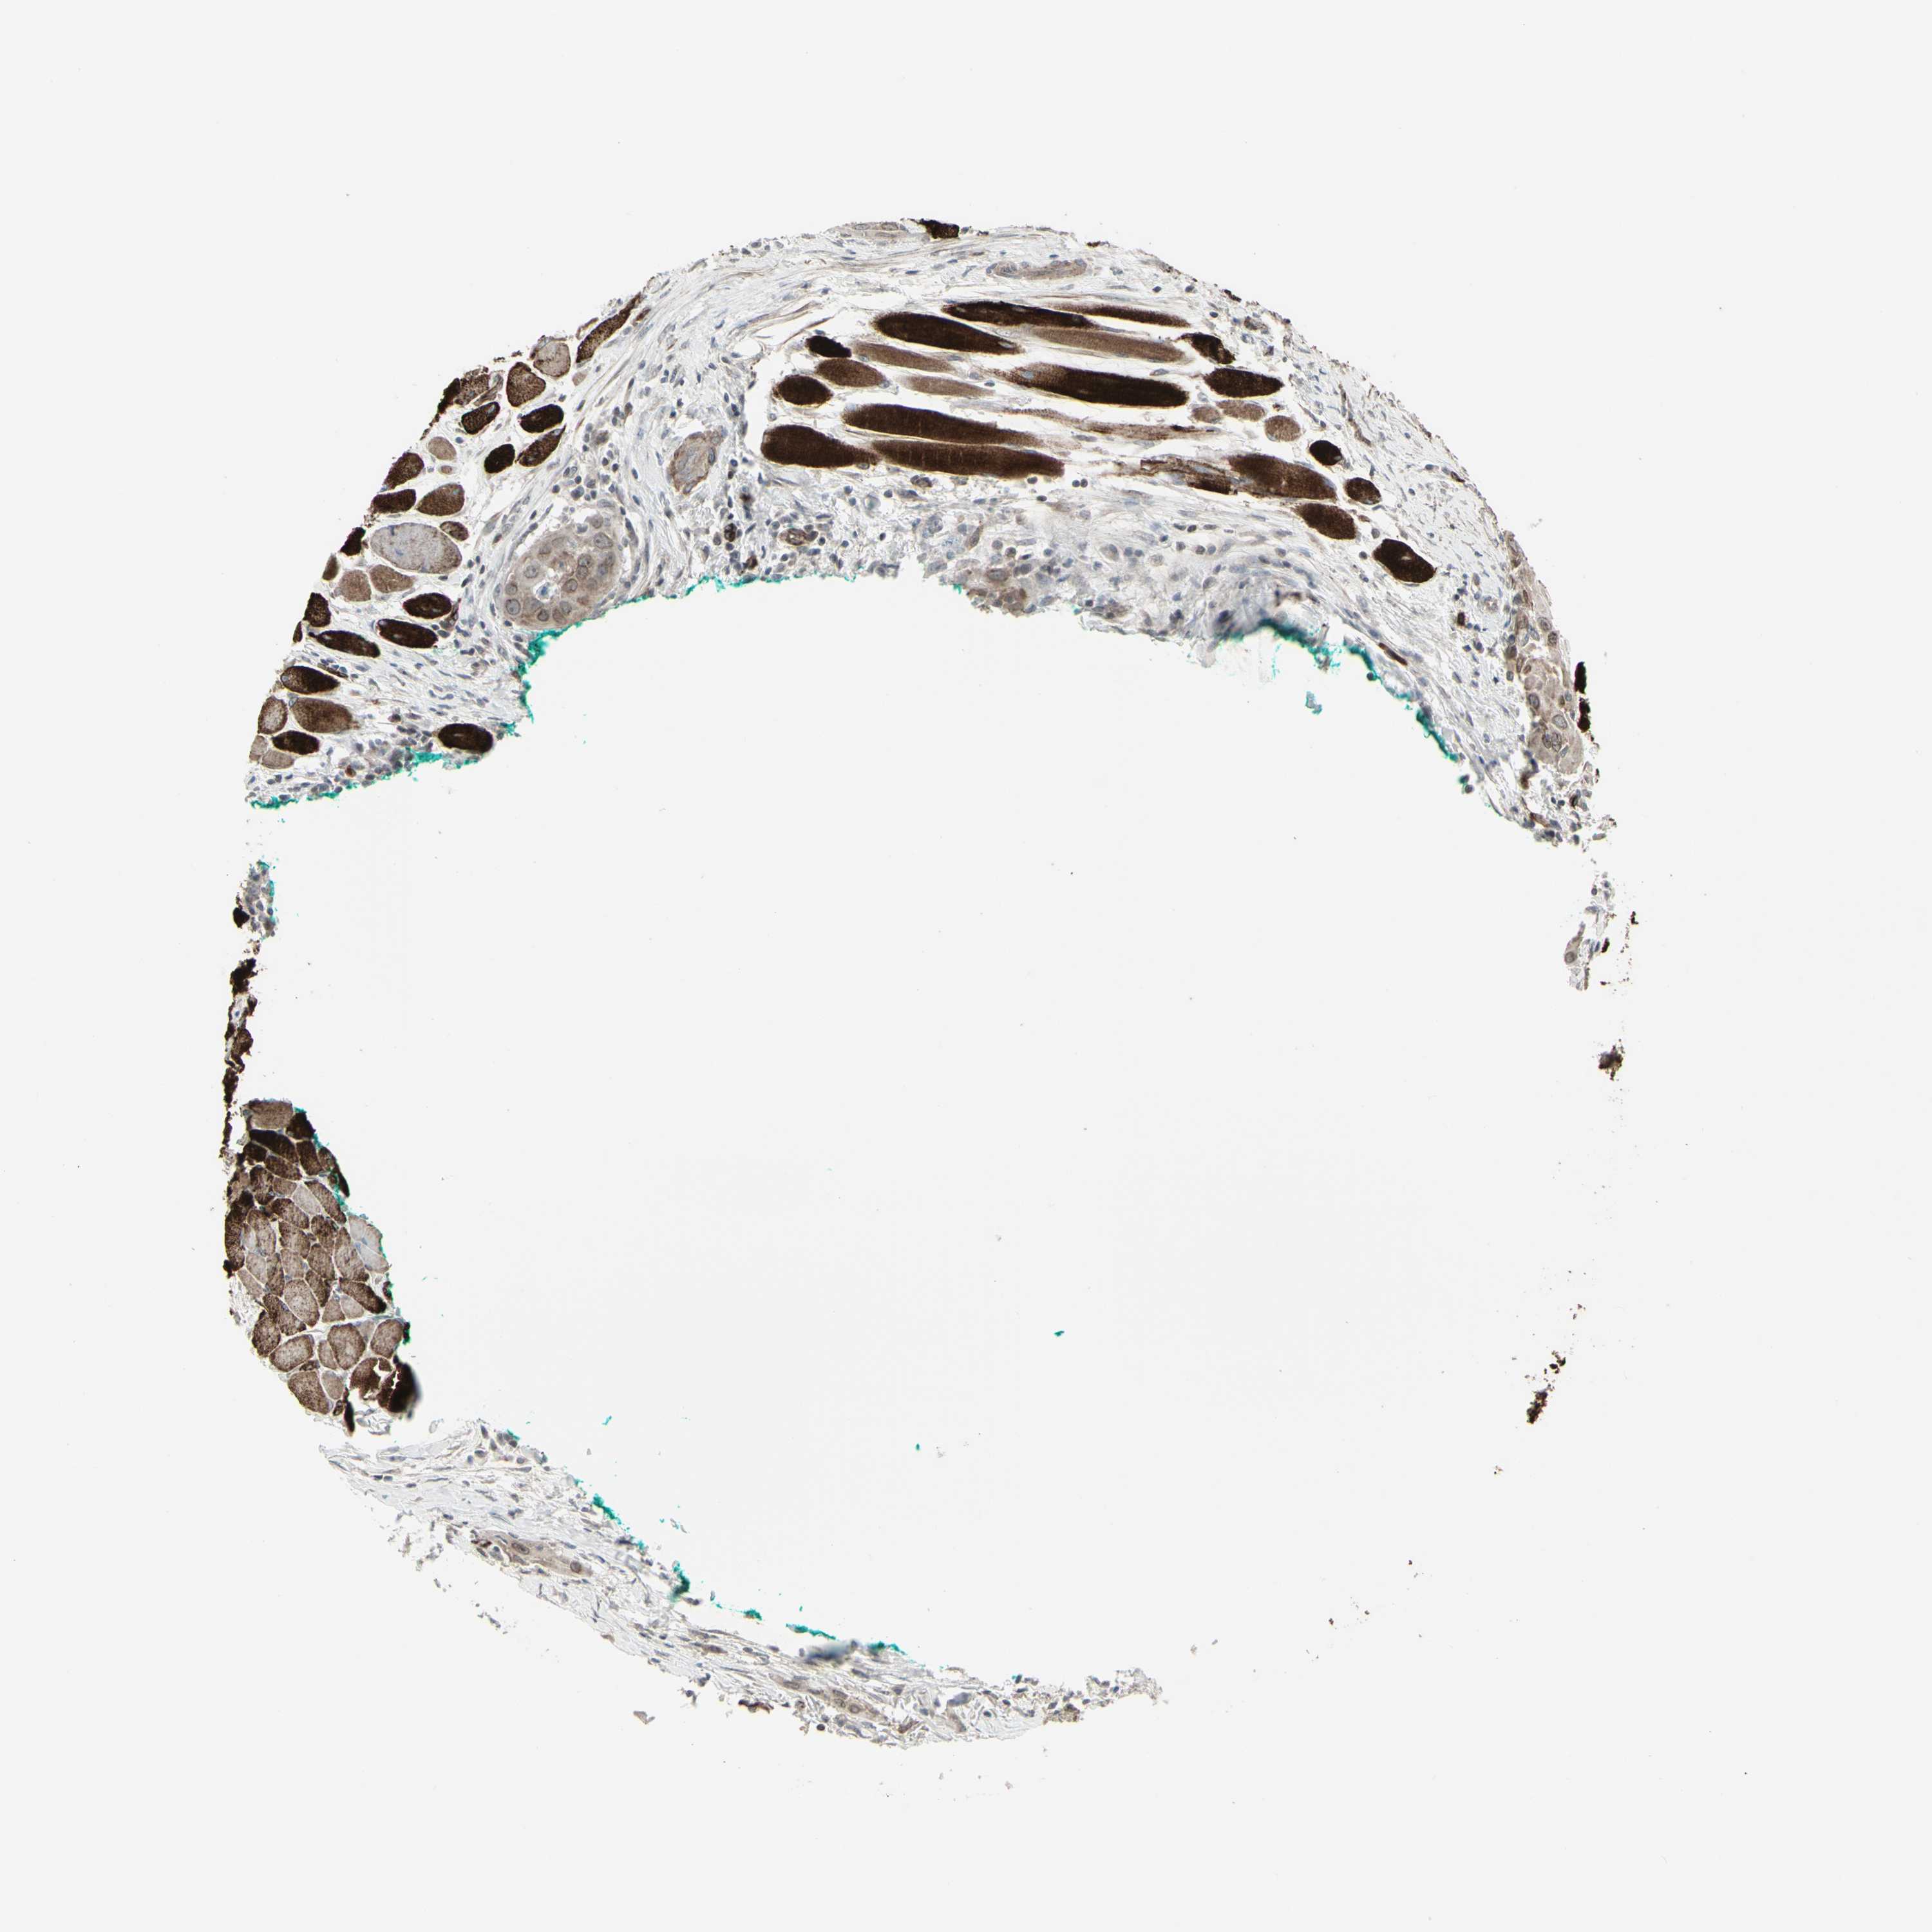

HEAD AND NECK CANCER - Protein expressioni

A mouse-over function shows sample information and annotation data. Click on an image to view it in a full screen mode. Samples can be filtered based on level of antibody staining by selecting one or several of the following categories: high, medium, low and not detected. The assay and annotation is described here.

Antibody stainingi

Antibody staining in the annotated cell types in the current human tissue is reported as not detected, low, medium, or high, based on conventional immunohistochemistry profiling in selected tissues. This score is based on the combination of the staining intensity and fraction of stained cells.

Each image is clickable and will lead to virtual microscopy that enables deeper exploration of all samples and also displays staining intensity scores, fraction scores and subcellular localization as well as patient and tissue information for each sample.

Antibody HPA010570

Staining

High

Medium

Low

Not detected

Intensity

Strong

Moderate

Weak

Negative

Quantity

>75%

75%-25%

<25%

None

Location

Nuclear

Cytoplasmic/membranous

Cytoplasmic/membranous,nuclear

Squamous cell carcinoma, NOS